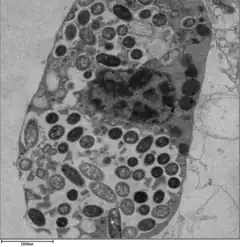

For Legionella to survive within macrophages and protozoa, it must create a specialized compartment known as the Legionella-containing vacuole (LCV). Through the action of the Dot/Icm secretion system, the bacteria are able to prevent degradation by the normal endosomal trafficking pathway and instead replicate. Shortly after internalization, the bacteria specifically recruit endoplasmic reticulum-derived vesicles and mitochondria to the LCV while preventing the recruitment of endosomal markers such as Rab5a and Rab7a. Formation and maintenance of the vacuoles are crucial for pathogenesis; bacteria lacking the Dot/Icm secretion system are not pathogenic and cannot replicate within cells, while deletion of the Dot/Icm effector SdhA results in destabilization of the vacuolar membrane and no bacterial replication.[25][26]